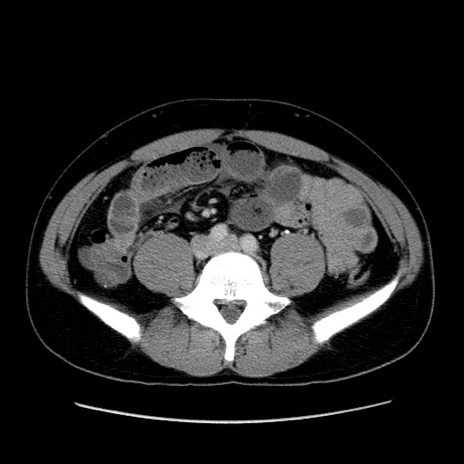

症例4(横断像)

【症例】30歳代男性

【主訴】腹痛、嘔吐

【現病歴】昨晩から突然の腹痛あり、その後嘔吐、軟便も出現。腹痛が改善しないため救急搬送となる。2日前にしめ鯖の食事歴あり。

【身体所見】意識清明、苦悶様、BP 135/90mmHg、BT 35.7℃、腹部:平坦、やや硬、心窩部〜臍部に自発痛、圧痛あり、筋性防御+、反跳痛-

【データ】WBC 8100、CRP 0.57